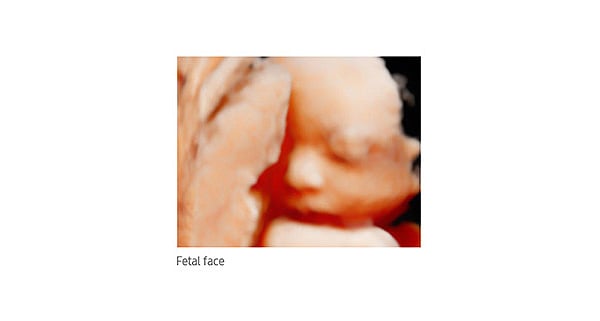

The HM70 EVO delivers high-performance portable imaging for diverse clinical applications, built on five core pillars: Versatility, Stability, Intuitiveness, Durability, and Mobility. This comprehensive system provides streamlined workflow, exceptional durability, and high-resolution imaging across various clinical environments to meet today's demanding healthcare requirements.